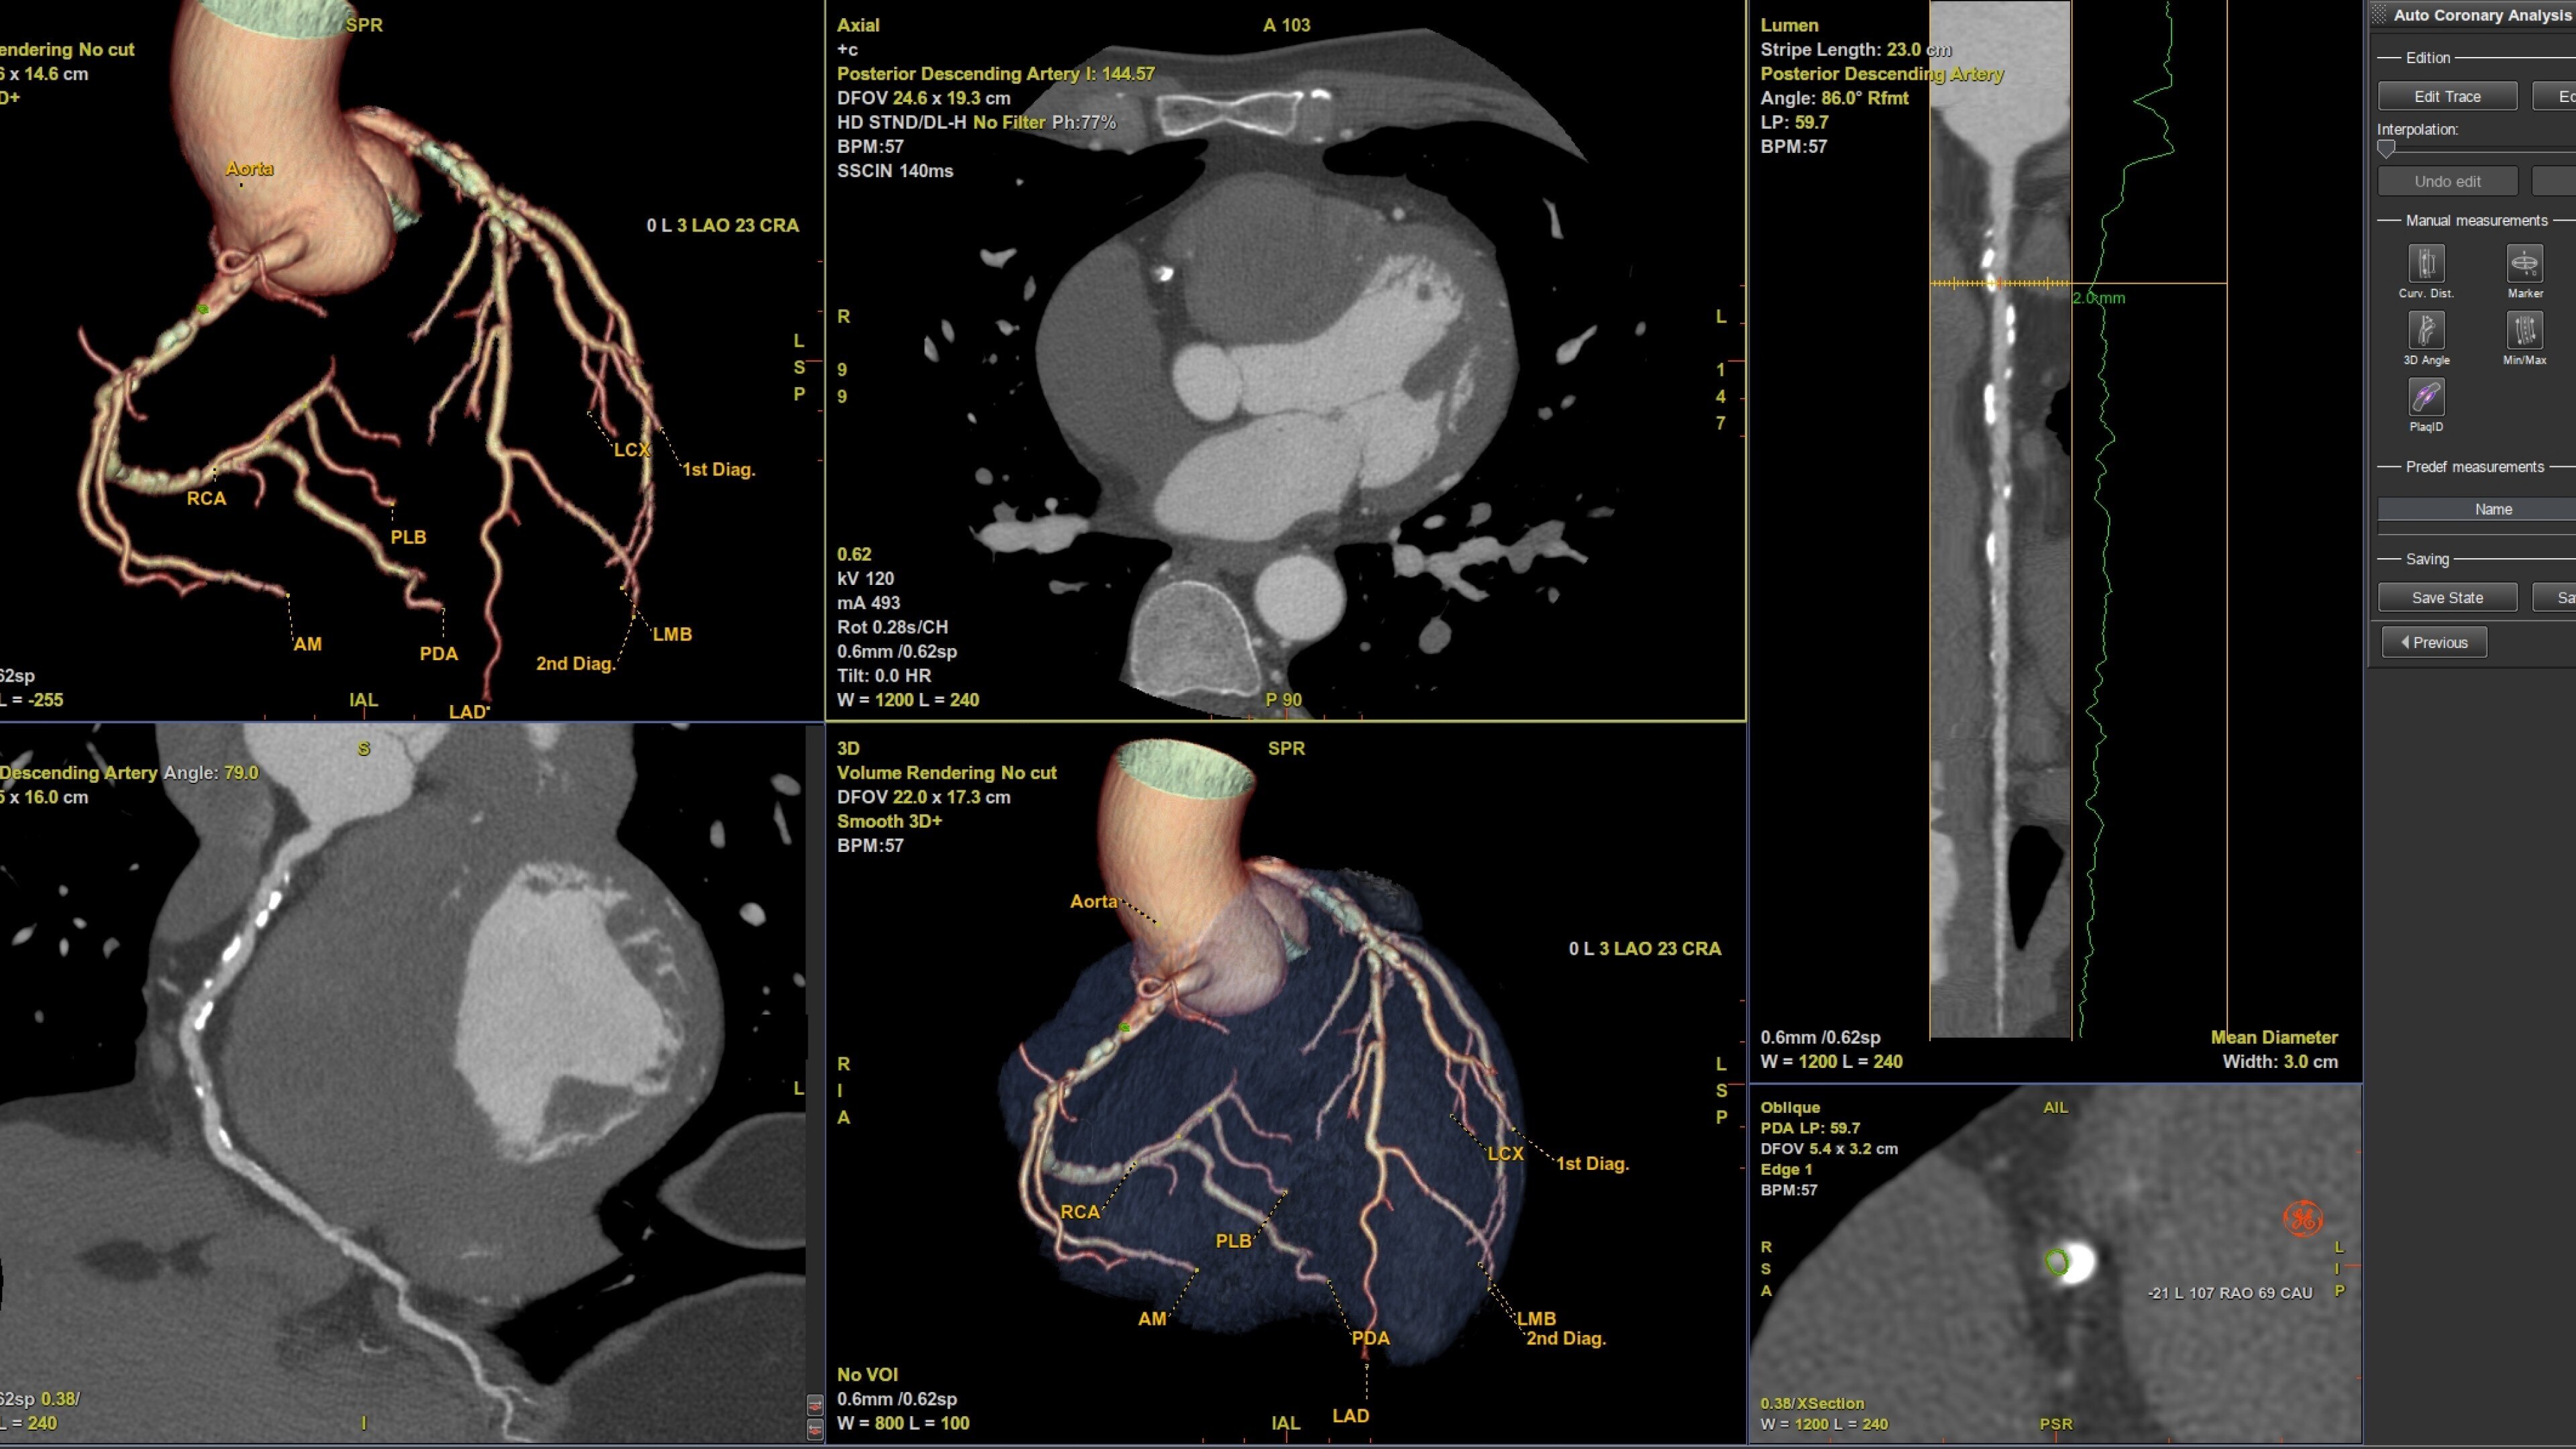

• Pre-processing automatically recognizes cardiac datasets and performs all segmentations as data arrives on the system saving processing time

• Auto Coronary analysis automatically segments the coronary tree, tracks and labels the coronary arteries

• Automatic extraction of the left ventricle across all phases and the automatic detection of systole and diastole delivers calculated ejection fraction and stroke volumes